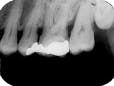

When the zygomatic process of the maxilla is superimposed on the roots of the maxillary molars (see Radiograph 4), another error occurs frequently with either technique. Too much vertical angulation will show this error in bisecting. Decreasing the vertical angulation by at least 10 degrees corrects it. With parallel technique, the key factor is improper placement of the film holder. Change the position of the film holder so the biting surface is flush with the occlusal and incisal surfaces.